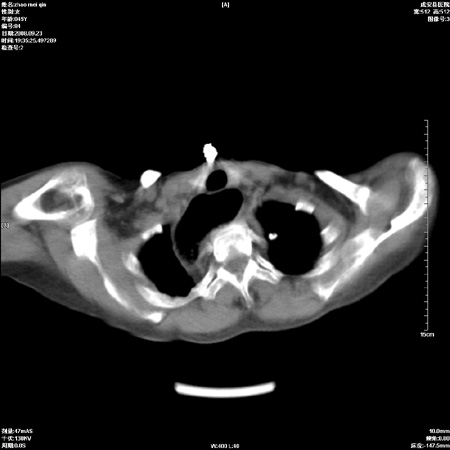

标题: CT15861:女 60 外伤后1小时 胸疼 [打印本页]

标题: CT15861:女 60 外伤后1小时 胸疼

外伤后1小时 胸疼 是外伤后引起的吗?

食道扩张明显下端逐渐变窄,倒像贲门失迟缓

非外伤性改变,典型的贲门失迟缓症

食道扩张明显下端逐渐变窄,大量食物存留,象贲门失迟缓症。